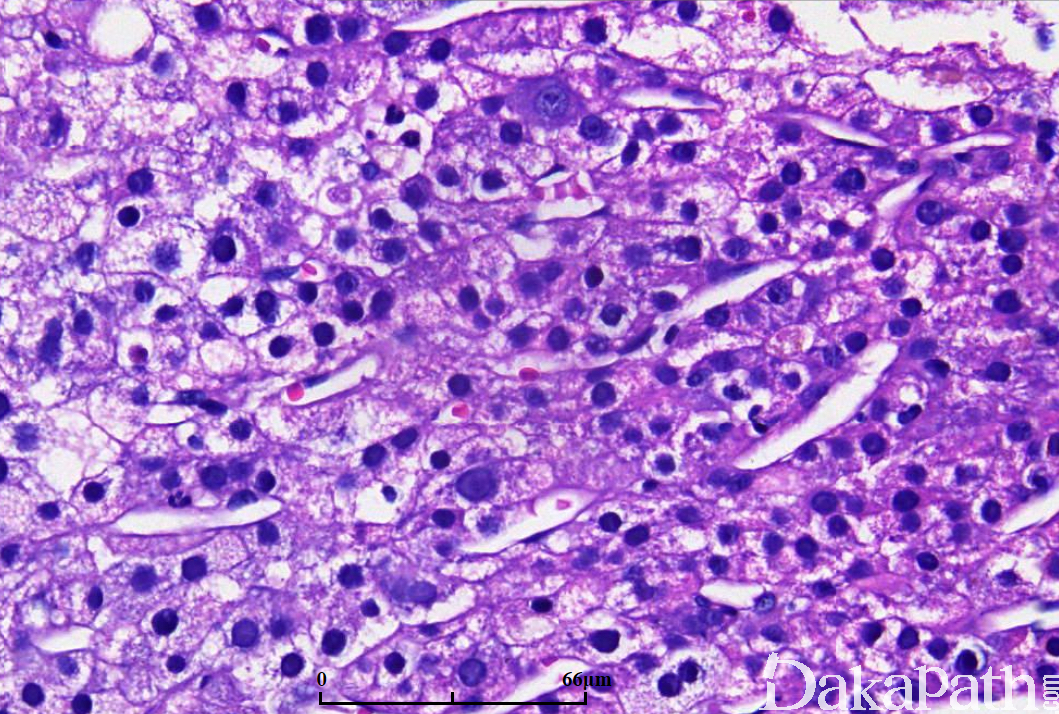

主要有三种组织结构,梁状、腺泡状和实体型:

a)梁状结构由 3 层以上细胞组成,周围围绕扁平内皮细胞,无 kupffer 细胞;

b)腺泡结构由实心细胞巢中央区域退变形成假腺样结构,腔内为胶样物,也可以由扩张的胆管形成腺样结构;

肿瘤细胞常类似肝细胞,通常体积较大,多角形,核空泡状,位于中央,可有核仁;

肿瘤细胞产生胆汁是肝细胞癌特征性病变;

间质为毛细血管化的肝窦,被覆扁平内皮细胞,CD34 染色阳性;

b)中分化:肝细胞索宽度 4 个细胞以上,细胞体积较正常肝细胞大,胞质嗜酸性,核仁突出,可见假腺样结构和瘤巨细胞;